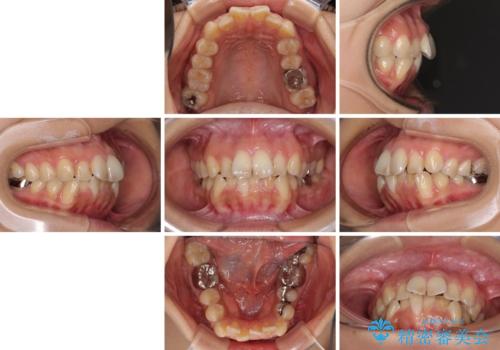

デコボコと口元の突出感 ハーフリンガルでの抜歯矯正

- 前歯のデコボコと上顎の前突感による口の閉じにくさを気にして来院された患者様です。

目立たない装置を希望されたので、上顎が裏側装置のハーフリンガルを選択し、上下左右の小臼歯(計4歯)を抜歯して矯正治療を行うこととしました。

表側のワイヤー矯正に比べると治療期間は長く、費用も高額となりますが、どうしても目立たせたくないという方にはお勧めの抜歯矯正です。